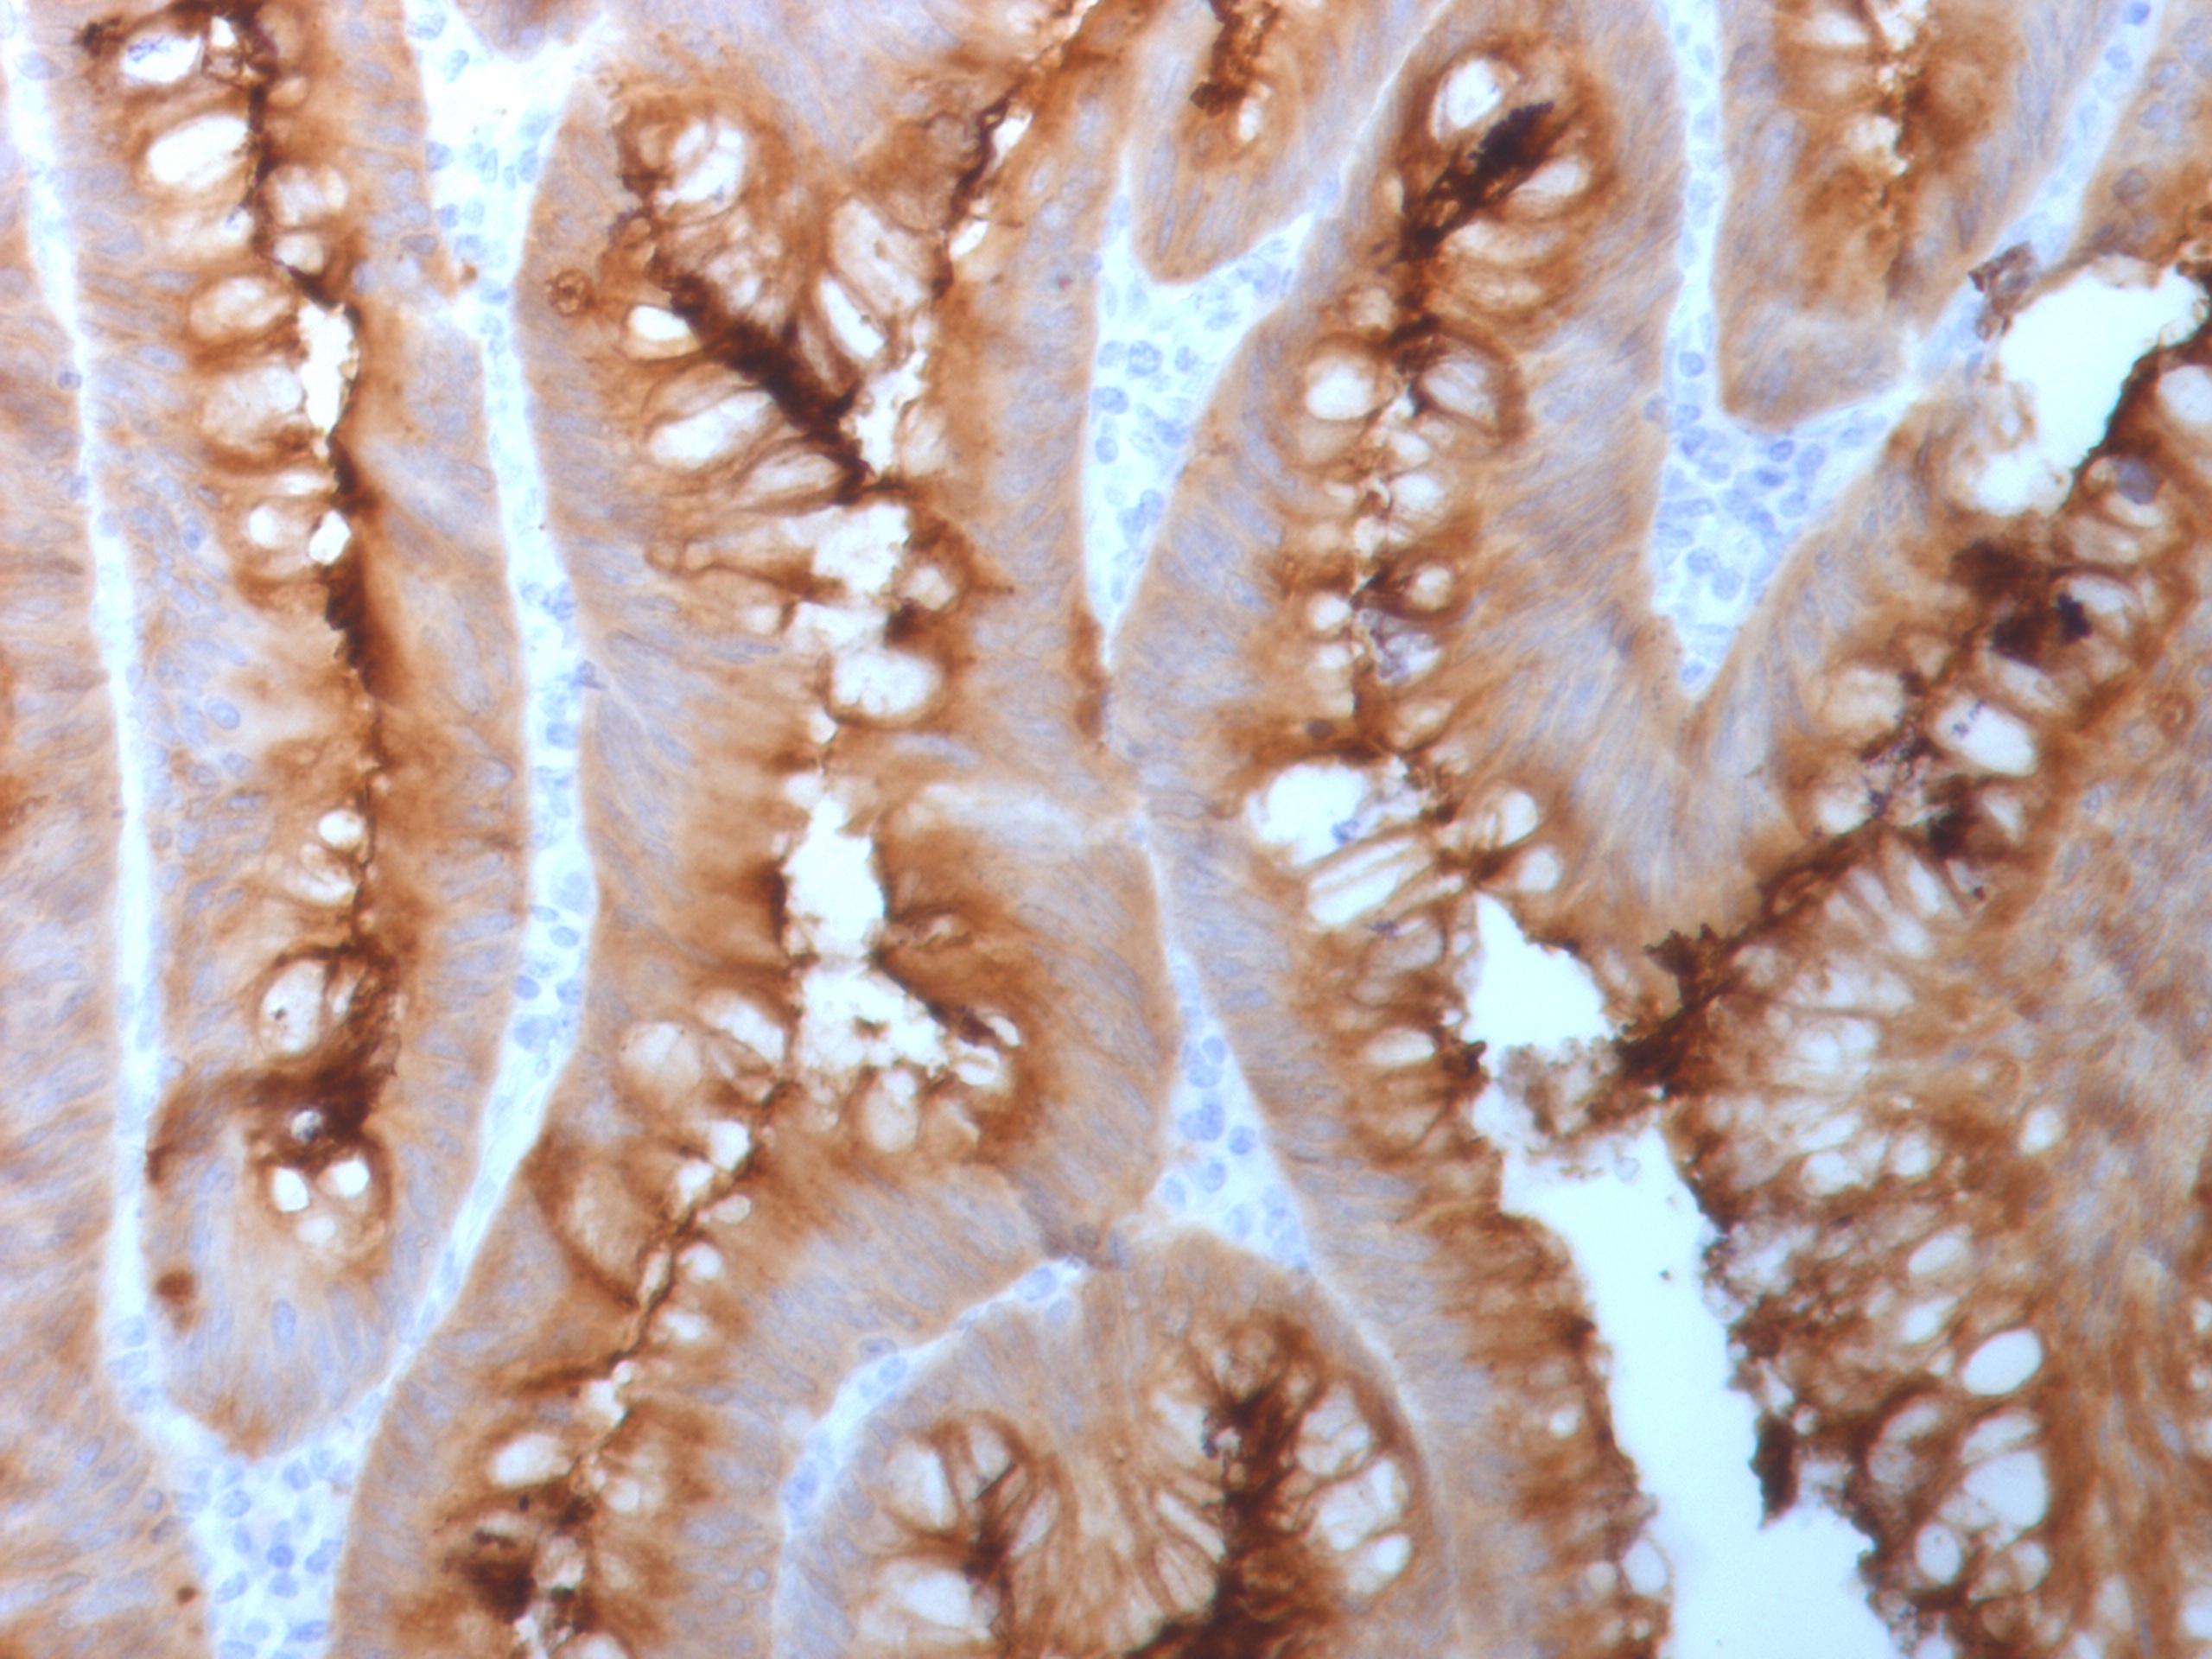

Formalin-fixed, paraffin-embedded human colon carcinoma stained with CEA Rabbit Recombinant Monoclonal Antibody (C66/1983R). Inset: PBS instead of primary antibody; secondary only negative control.

This antibody recognizes proteins of 80-200kDa, identified as different members of CEA family. CEA is synthesized during development in the fetal gut and is re-expressed in increased amounts in intestinal carcinomas and several other tumors. This MAb does not react with nonspecific cross-reacting antigen (NCA) and with human polymorphonuclear leucocytes. It shows no reaction with a variety of normal tissues and is suitable for staining of formalin/paraffin tissues. CEA is not found in benign glands, stroma, or malignant prostatic cells. Antibody to CEA is useful in detecting early foci of gastric carcinoma and in distinguishing pulmonary adenocarcinomas (60-70% are CEA+) from pleural mesotheliomas (rarely or weakly CEA+). Anti-CEA positivity is seen in adenocarcinomas from the lung, colon, stomach, esophagus, pancreas, gallbadder, urachus, salivary gland, ovary, and endocervix.